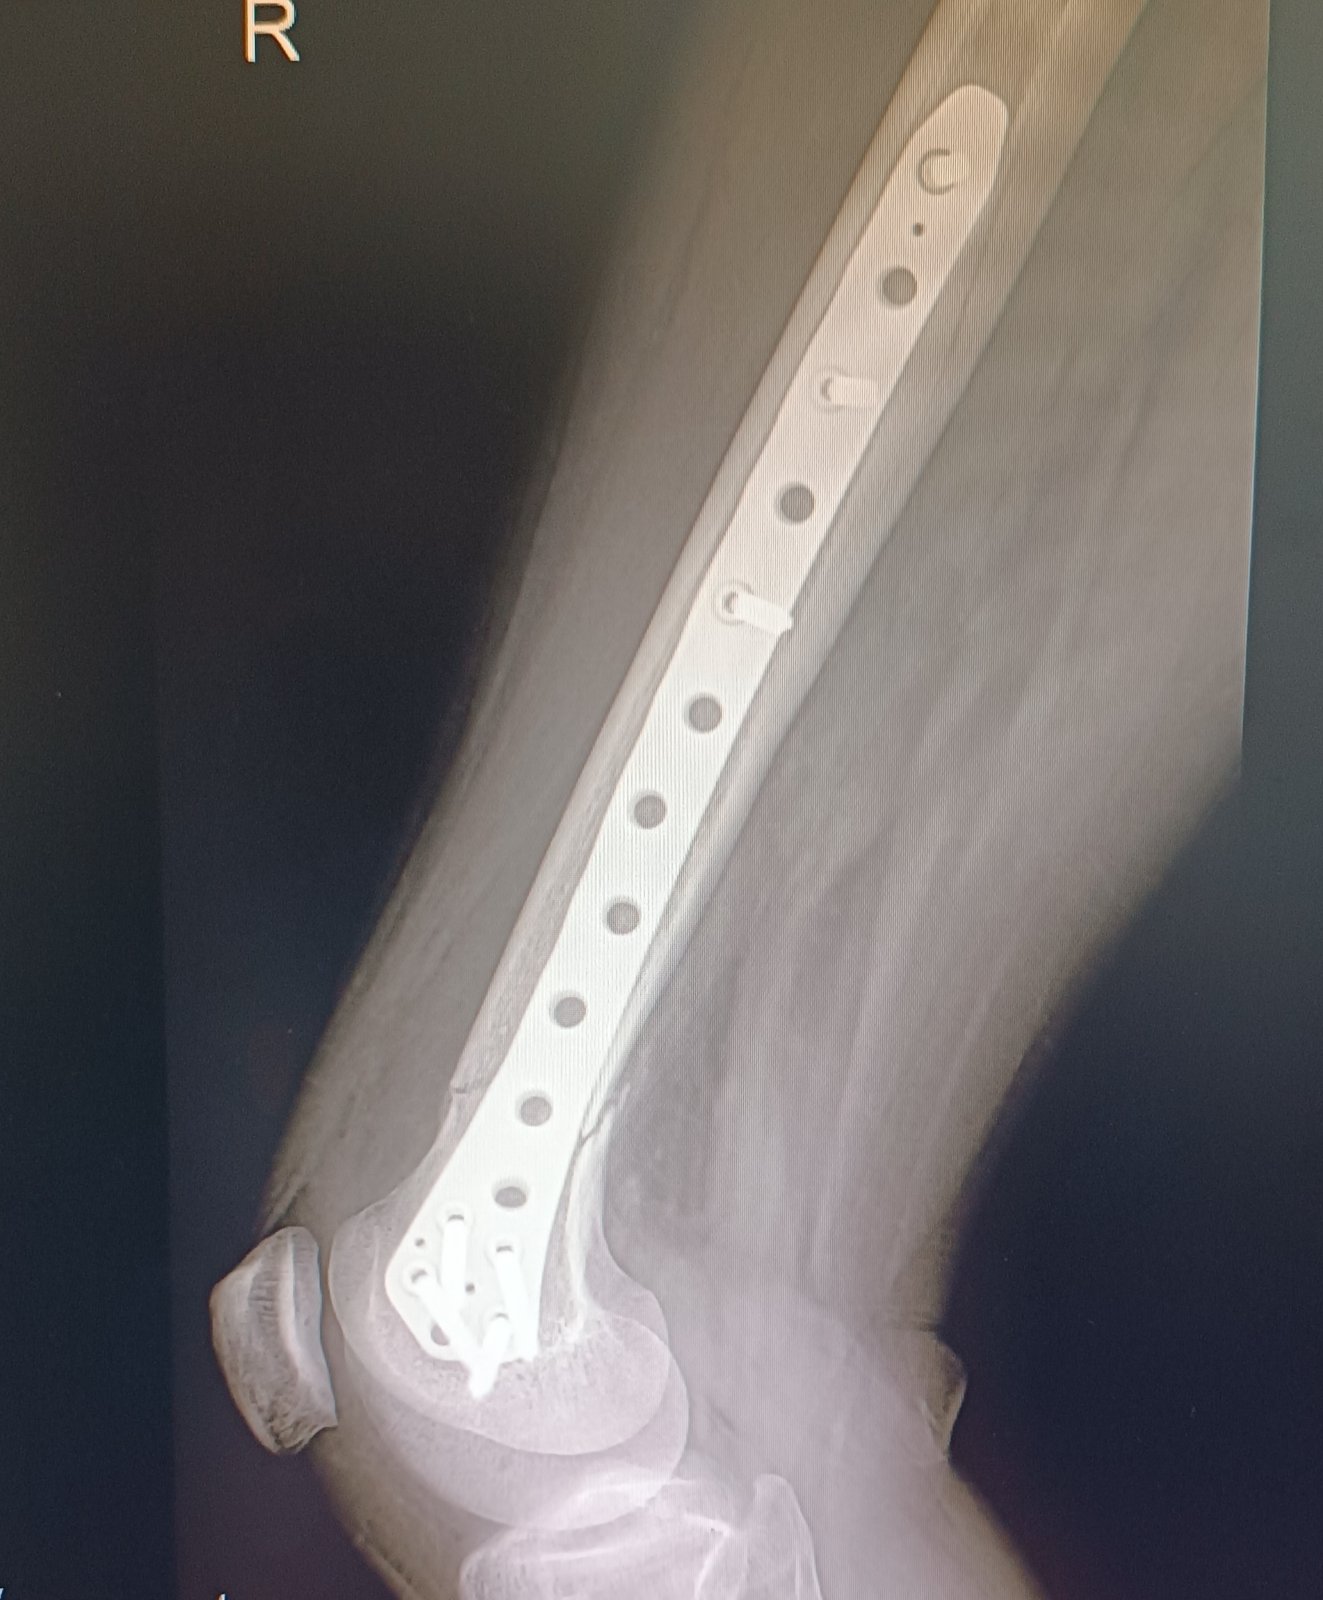

@minenkaa aj mne dávajú na výber jeden doktor bol zato vybrať kvôli veku a tomu že pri dlhšej chodzi mi začne platnička tlačiť na koleno a boli ma skôr sa mi zdalo že v zime to bolo viac ..dnes som bola už teda dohodnúť operaciu a tam iny doktor že by to tam možno aj nechal že na mojom mieste že zas mi to narežu v mieste jazvy a narušia tkaniva a niekedy sa to ani nejak nezlepší že keď tam už bolo zranenie neviem sama čo robiť som s toho na nervy 🙁bojim sa operácie hrozne ale aj toho že mi tam ta platnička bude vadiť keď nastupim do prace ešte som na materskej

@anonym_a80ec7 ano po prvej operácii som si vravela že nikdy viacej že to tam necham navždy ale teraz ..vaham lebo ma boli koleno z toho keď dlho chodim ta platnička tlačí naň preto zvažujem vybratie viem že to tam môže byť navždy len sa bojim aby mi to neskôr nerobilo vetšie problemy .